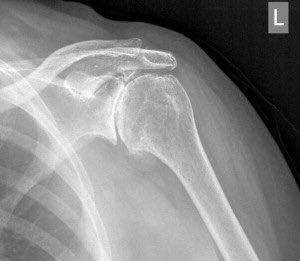

🔵 الكتف المتجمدة ( تيبس الكتف )

ألم في مفصل الكتف وتيبسه. عادة ما تبدأ العلامات والأعراض تدريجياً، حيث تزداد سوءً بمرور الوقت ثم تنحسر الأعراض تدريجيا بالعلاج، وعاده ما يستغرق ذلك عاما إلى ثلاثة أعوام.